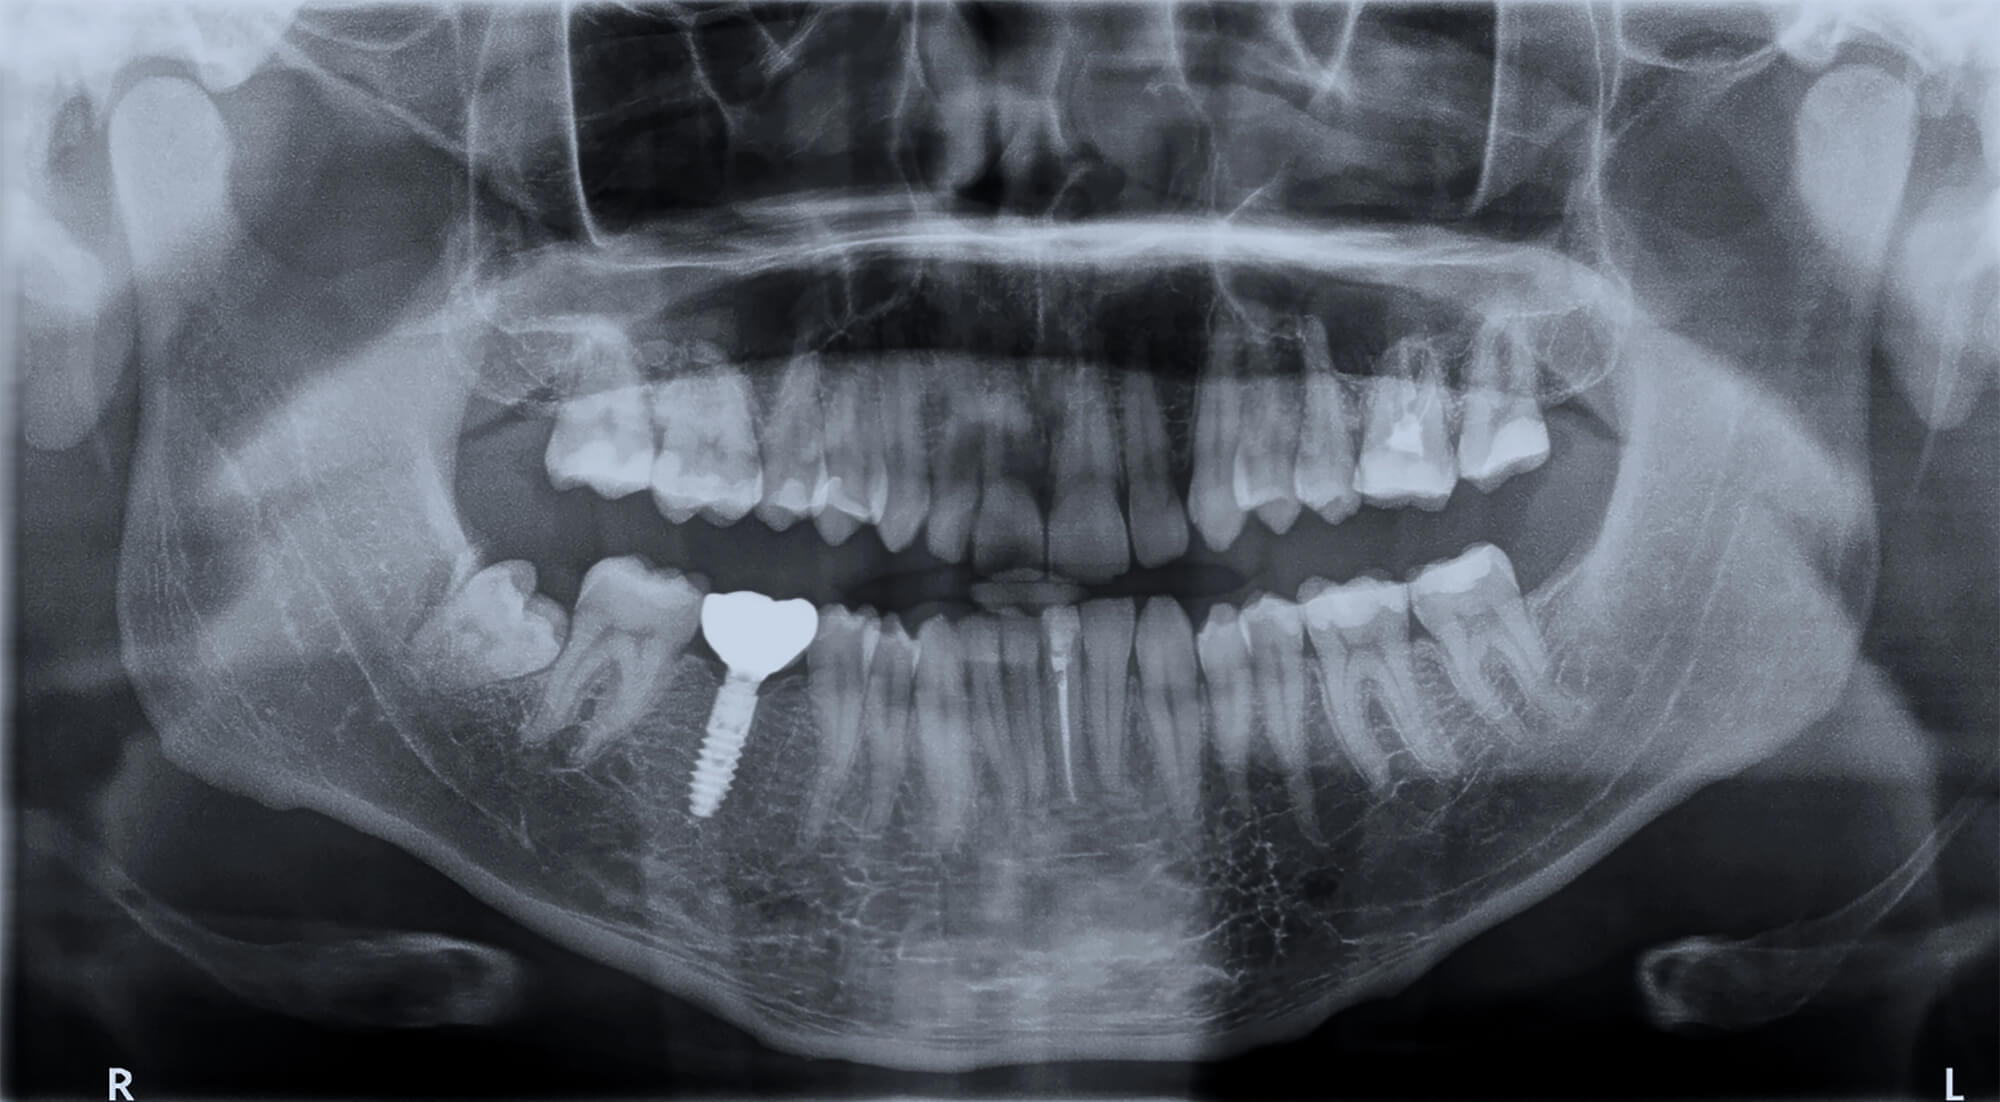

Diagnostic Imaging

- Intraoral radiographs (periapical or bitewing) to check for bone loss

- Digital imaging or CBCT scan to assess the implant’s position, surrounding bone, and integrity of osseointegration

These tools help your dentist identify whether the issue stems from soft tissue inflammation, peri-implantitis, mechanical complications, or more complex bone-related concerns.